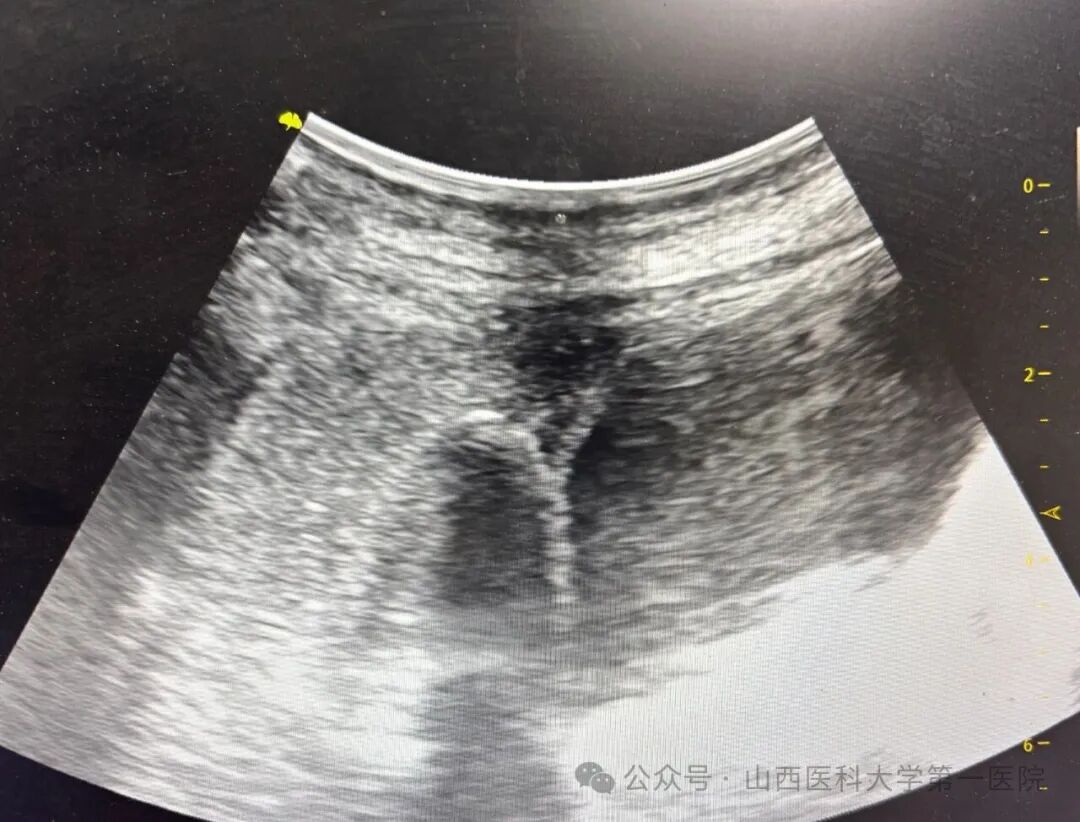

患者入院后,肿瘤综合科经过疑难病例微创术前讨论一致认为,该患者化疗联合免疫治疗失败,如及时实施局部消融治疗,能够带来生存和生活质量双获益,但是肿瘤所在位置为胆囊窝,解剖结构十分复杂,如果实施常规热消融,则术中90-300°C的热量弥散会导致局麻患者术中剧烈疼痛难以忍受,且术后胆瘘发生率极高,根据目前经皮冷冻消融治疗中国专家共识相关推荐条款,完成知情同意流程后,遂决定采取-150°C超声引导局部麻醉下胆囊窝肿物冷冻消融治疗术。手术全程患者无明显疼痛及腹胀加重,意识清醒,可随时与操作医生保持良好沟通,经过两次-150°C冷冻循环,60min操作过程,手术顺利完成。